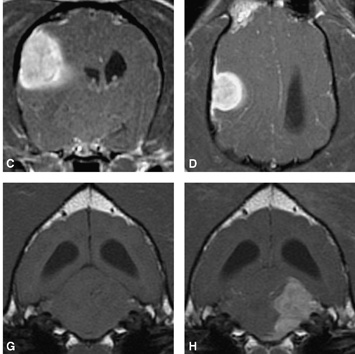

La risonanza magnetica risulta insostituibile come esame nelle lesioni cerebrali in particolare per lo studio dell'epilessia primaria o idiopatica, nello studio come le malformazioni congeniti quali l'idrocefalo nel cucciolo in età di sviluppo, nel tumore primario celebrale (meningiomi, gliomi, blastomi) o nelle metastasi cerebrali, nella malformazione come la sindrome di Chiari (particolarmente colpita la razza del Kink Cavalier). Nelle emoragie craniche post-traumatiche, nello studio dell'adenoma della ghiandola ipofisaria, nello studio dell'area retrobulbare oculare.